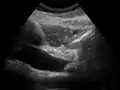

On abdominal ultrasonography, the common bile duct is most readily seen in the porta hepatis (where the CBD lies anterior to the portal vein and hepatic artery). The absence of Doppler signal distinguishes it from the portal vein and hepatic artery.

Borderline of a dilated perihilar bile duct, measuring 8 mm.

Dilatation of CBD due to Ampullary tumor.